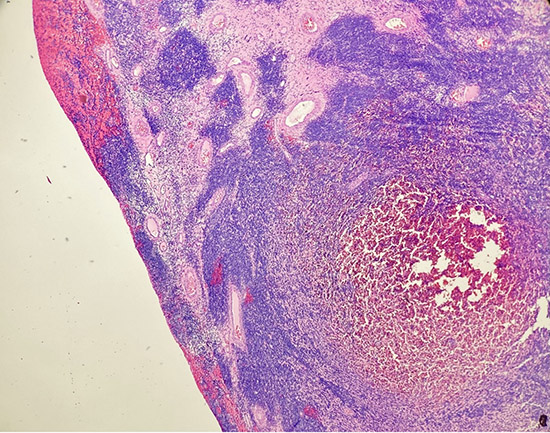

Tumor exhibits a densely cellular growth pattern with sheets and fascicles of atypical spindle cells infiltrating the full thickness of the myometrium, extending to the serosal surface (Low Magnification ,40X).